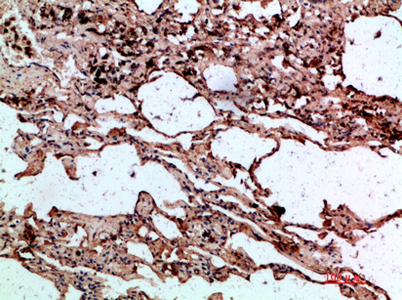

Product name: AAT rabbit pAb

Dilutions: Western Blot: 1/500 - 1/2000. IHC-p: 1:100-1:300. ELISA: 1/10000. Not yet tested in other applications.

Immunogen: The antiserum was produced against synthesized peptide derived from the N-terminal region of human SERPINA1. AA range:1-50